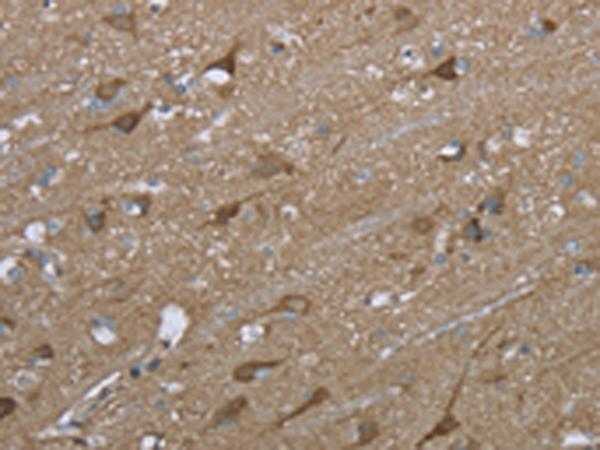

分类: 科研抗体货号: P08308别名: DRR1; TU3A应用: IHC反应种属: Human